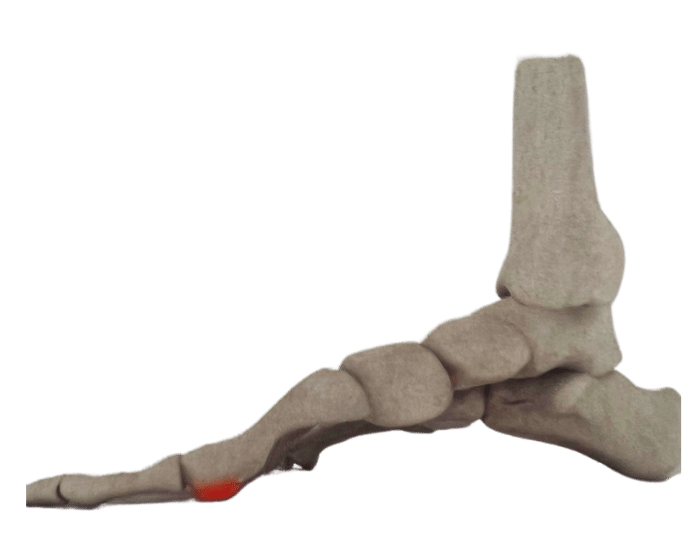

There are numerous reasons why you might need Custom Foot Orthotics. If you have pain in your foot, heel, knee or hip, have high arches or flat feet; or just being regularly on your feet and are getting any aches or pains in the feet or legs, or suffering from general foot pain while walking, running, playing sports or even at rest you qualify for Custom Foot Orthotics.